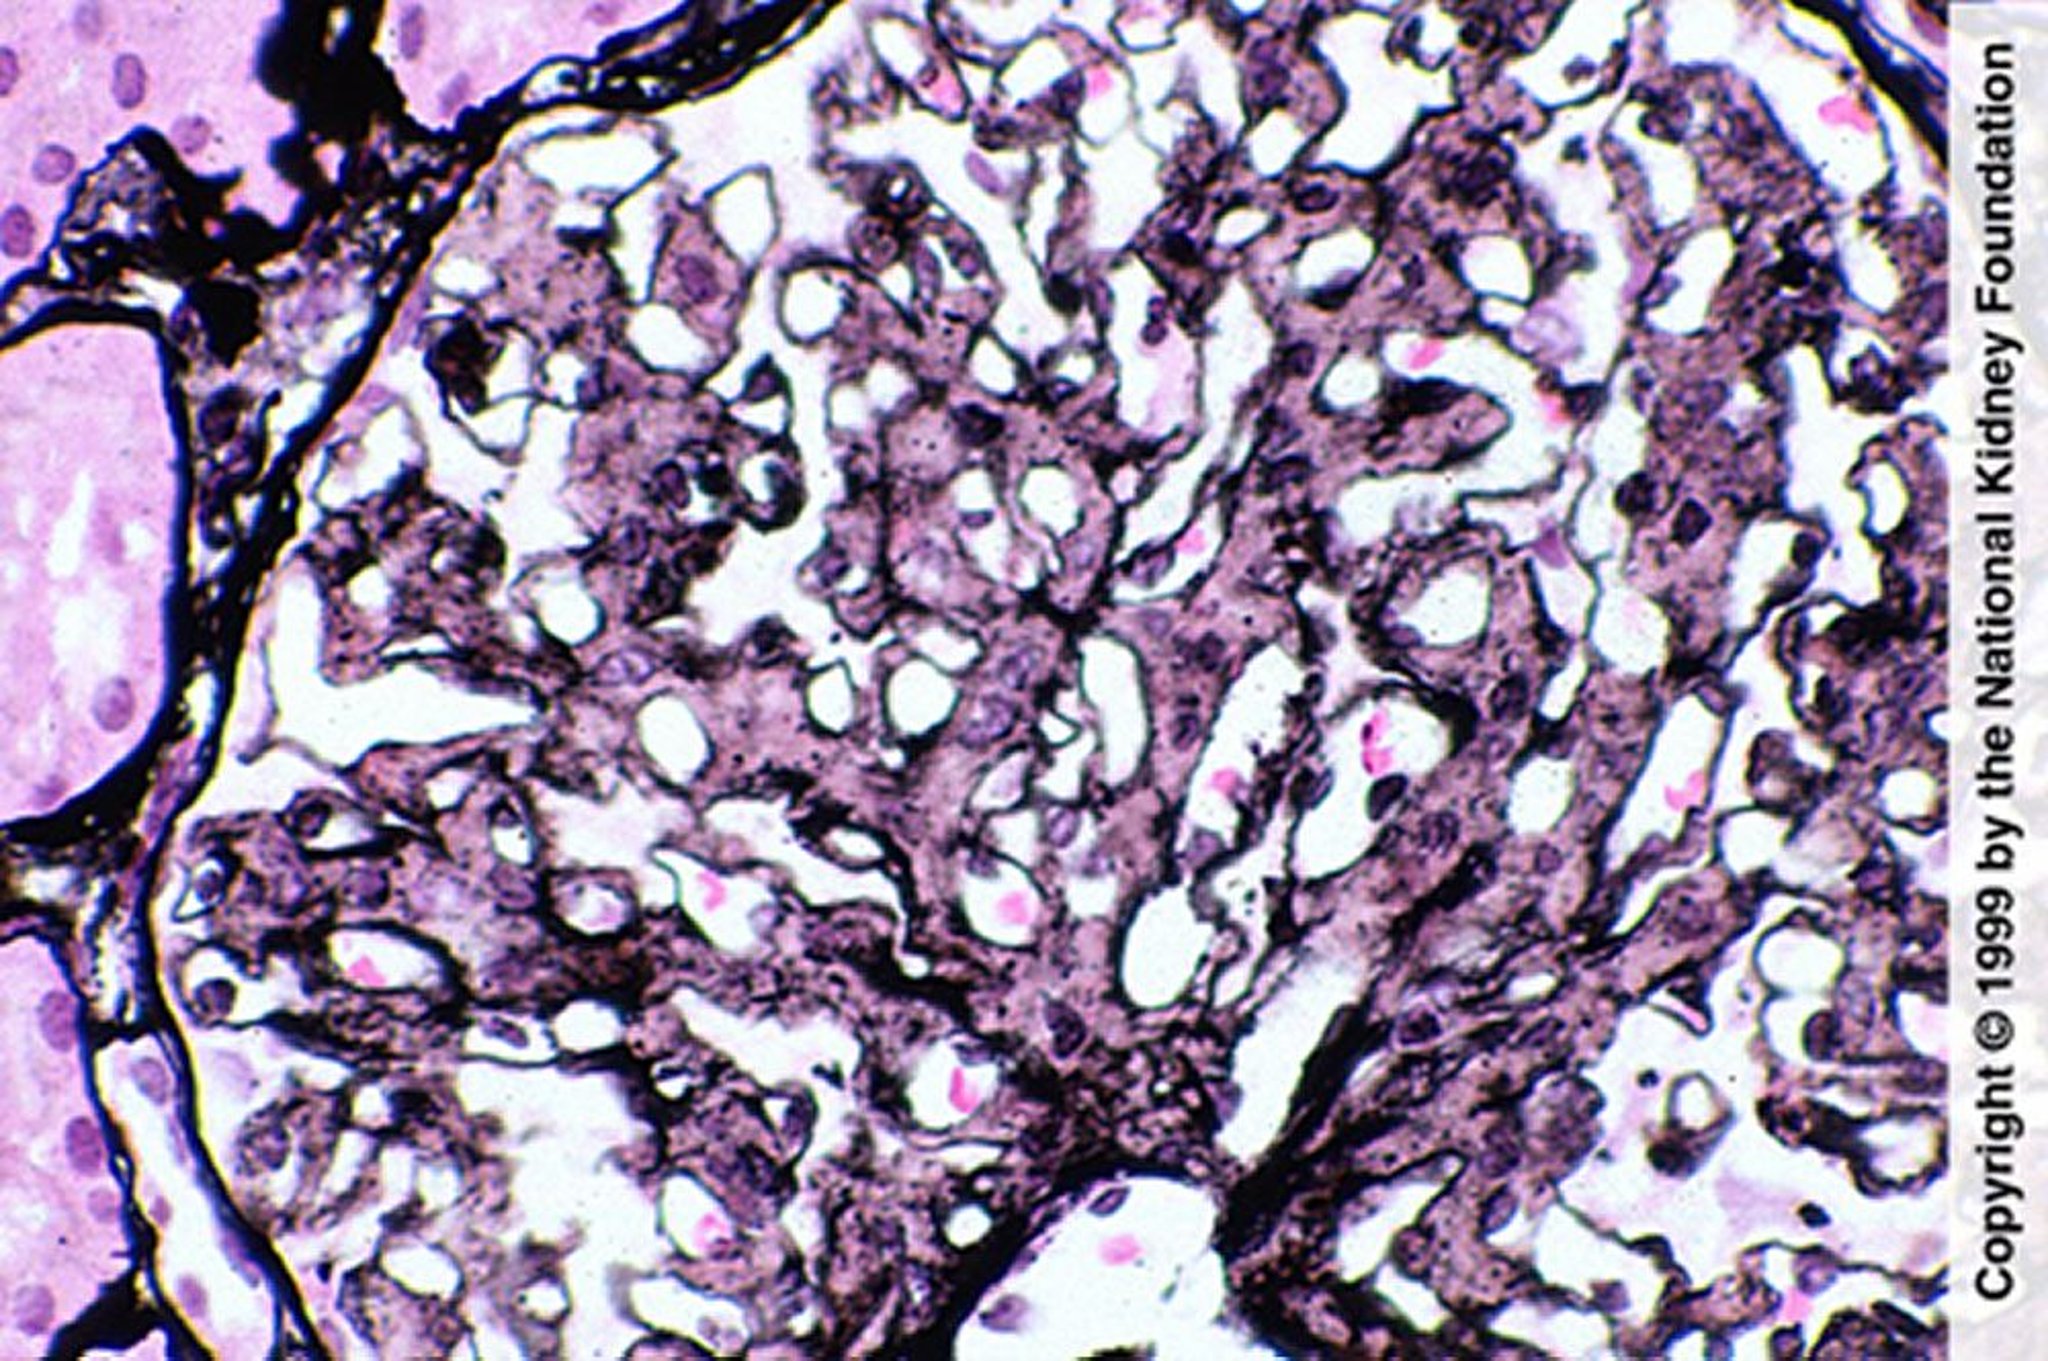

細線維性糸球体腎炎(メサンギウム増殖)

メサンギウム増殖は細線維性糸球体腎炎を示唆するが,診断にはコンゴレッド染色陰性,蛍光抗体法でのIgG染色,および電子顕微鏡で線維が認められることが必要である(PAM染色,400倍)。

Image provided by Agnes Fogo, MD, and the American Journal of Kidney Diseases' Atlas of Renal Pathology (see www.ajkd.org).